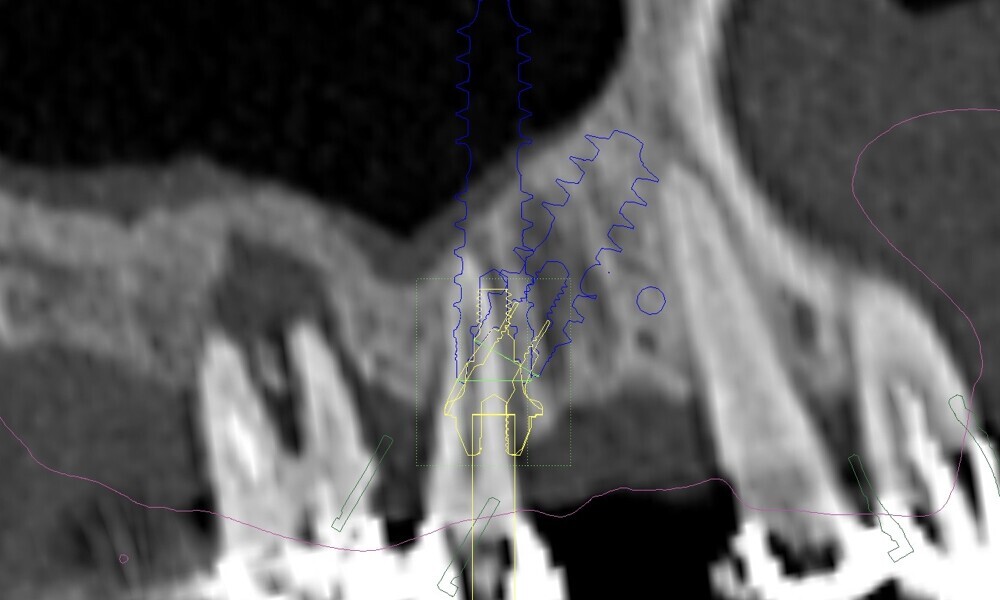

Compromised maxillary dentition treated with Straumann Pro Arch and a digital workflow